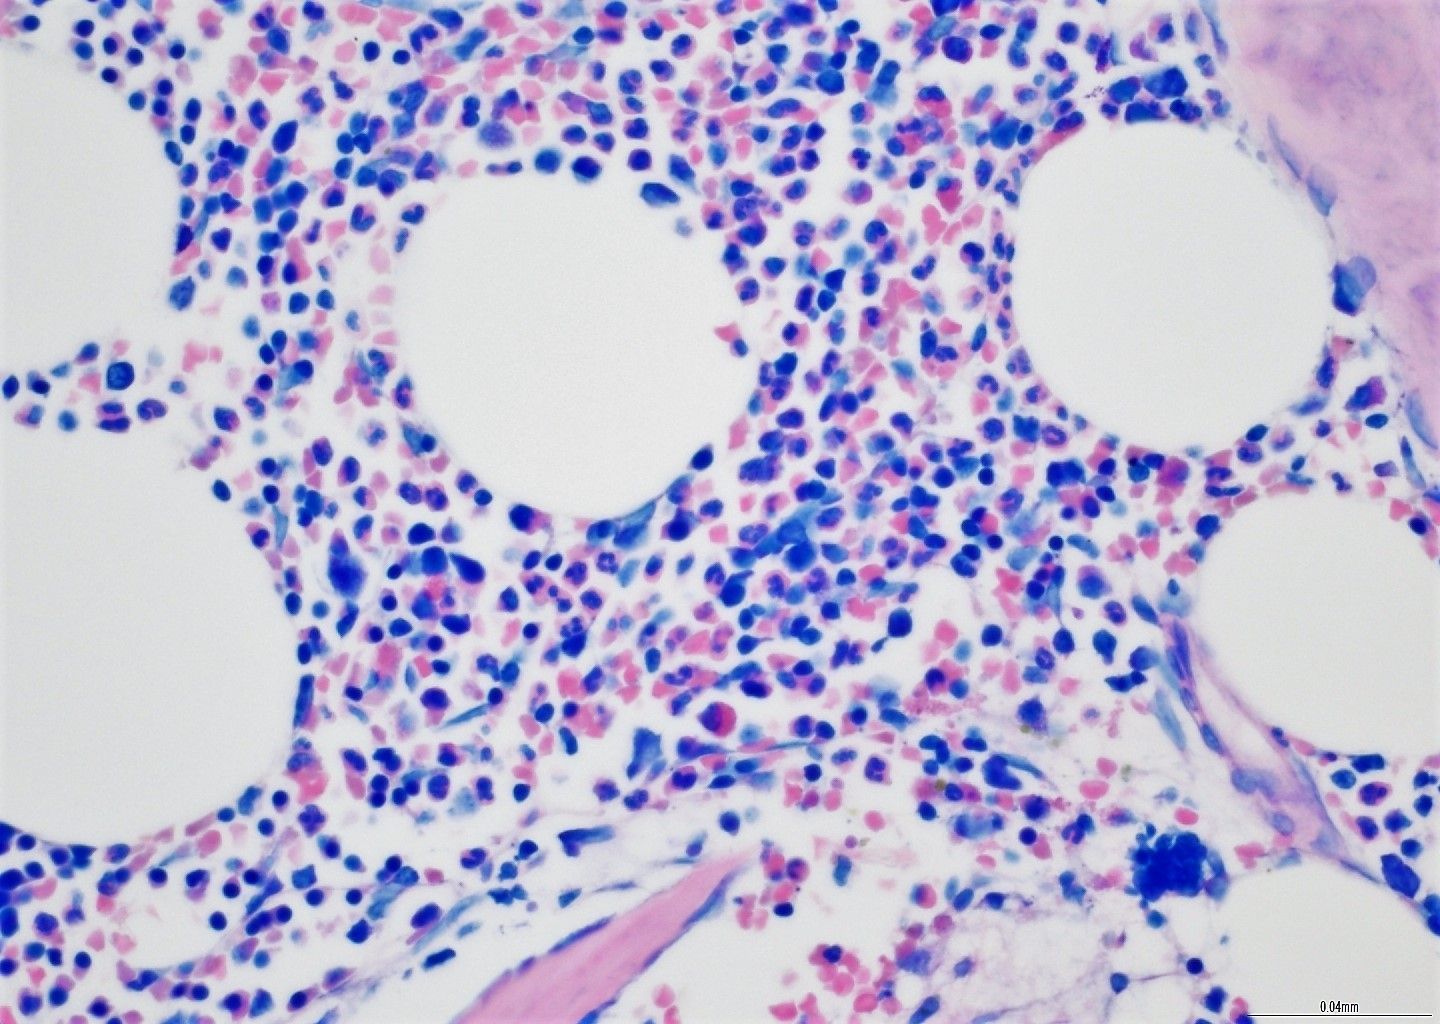

- Επίδειξη συγκεκριμένων στόχων αιμοσφαιρίων κατά τη βιοψία BMT